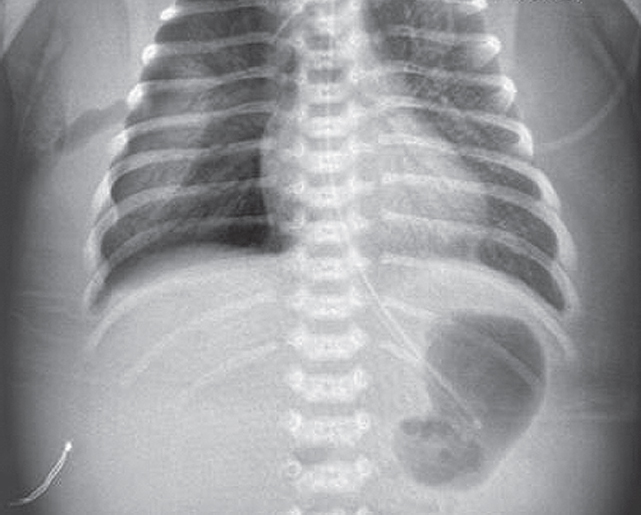

В левый главный бронх повторно введен порактант-альфа. После выполнения манипуляции отмечается клинико-рентгенологическое улучшение (рис. 4) — увеличение SpO2 до 90 %, положительная динамика газового состава крови.

Рис. 4. Рентгенограмма органов грудной клетки новорожденного после повторного монобронхиального введения сурфактанта

Fig. 4. Chest X-ray of newborn after repeated monobronchial administration of surfactant